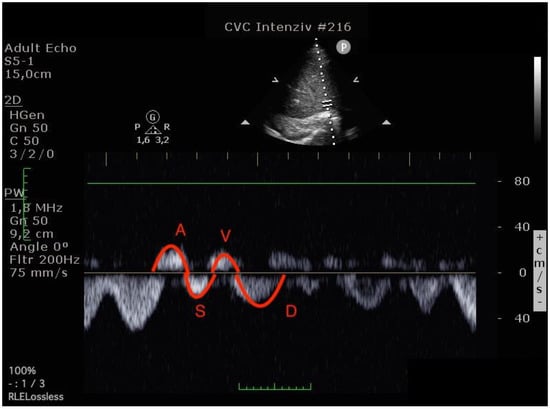

Blood flow was measured in the common hepatic vein right before draining into the inferior vena cava using pulse-waved Doppler ultrasound. The normal hepatic vein waveform has four components: a retrograde A, an anterograde S, a transitional V (which may be anterograde, retrograde, or neutral), and an anterograde D wave [,]. (Figure 2) We recorded the maximal velocities and velocity-time integrals (VTI) of the standard four waves (A, S, V, D) [,] (Figure 3 and Figure 4). The baseline ratios of the retrograde and anterograde waves were calculated preoperatively and their change in the postoperative measurement (20–24 h after surgery), is expressed as a delta ratio. The ratios of retrograde to anterograde VTIs were also calculated.

Figure 4.

Hepatic venous flow pattern (The left image was done before operation, the right image in the postoperative 24th hour. On the postoperative image, A and V waves appear increased, while the S wave is smaller than the D wave. (A VTI: 6.47 to 8.29, S VTI: 12.31 to 8.12, V VTI: 5.98 to 7.98 and D VTI: 11.12 to 9.39).